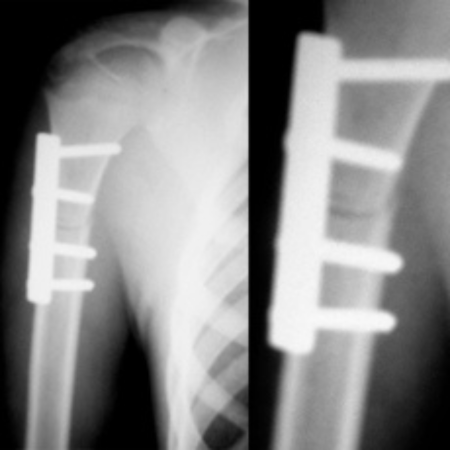

♦ Ендопротезиране: Извършва ендопротезиране на големи стави – тазобедрена, колянна и раменна – при травми, възпалителни заболявания и напреднало износване. Използват се висококачествени импланти на водещи световни компании като Zimmer, Mathys и Smith & Nephew.

♦ Незараснали и неправилно зараснали счупвания: Предлага възстановителни и реконструктивни операции при неправилно зараснали или незараснали счупвания на крайниците.